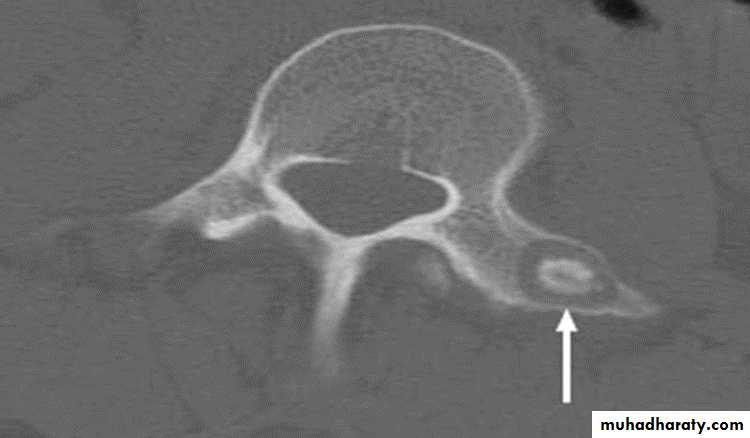

Ankylosing spondylitis-early

(A) Serrated marginsof sacroiliac joints and peri articular sclerosis.

(B) CT scanning demonstrates bilateral sacroiliitis